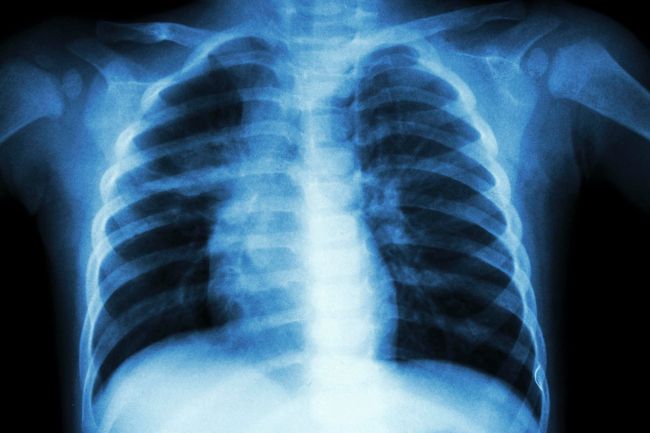

В Онкологическом центре имени Питера МакКаллама в Австралии провели тестирование системы IBM Watson – разработка позволила сократить время распределения пациентов с раком легких в подходящие клинические исследования.

В IBM сообщили, что на основе данных 102 пациентов система Watson мгновенно нашла для каждого из них 10 подходящих исследований с точностью в 92% по сравнению с подбором вручную, на который у врачей обычно уходит «несколько часов».

Представители центра отмечают, что тестирование заняло полгода и продемонстрировало потенциальные преимущества применения искусственного интеллекта для анализа «все более сложных» критериев участия в клинических испытаниях. Проект в Онкологическом центре имени Питера МакКаллама стал первым испытанием IBM Watson в Австралии.

Испытания IBM Watson в Центре МакКаллама прошли после подобного тестирования в Highland Oncology Group в США. В предыдущей программе система позволила сократить время отбора пациентов в клинические исследования на 78%, с 1 часа 50 минут (вручную) до 24 минут.